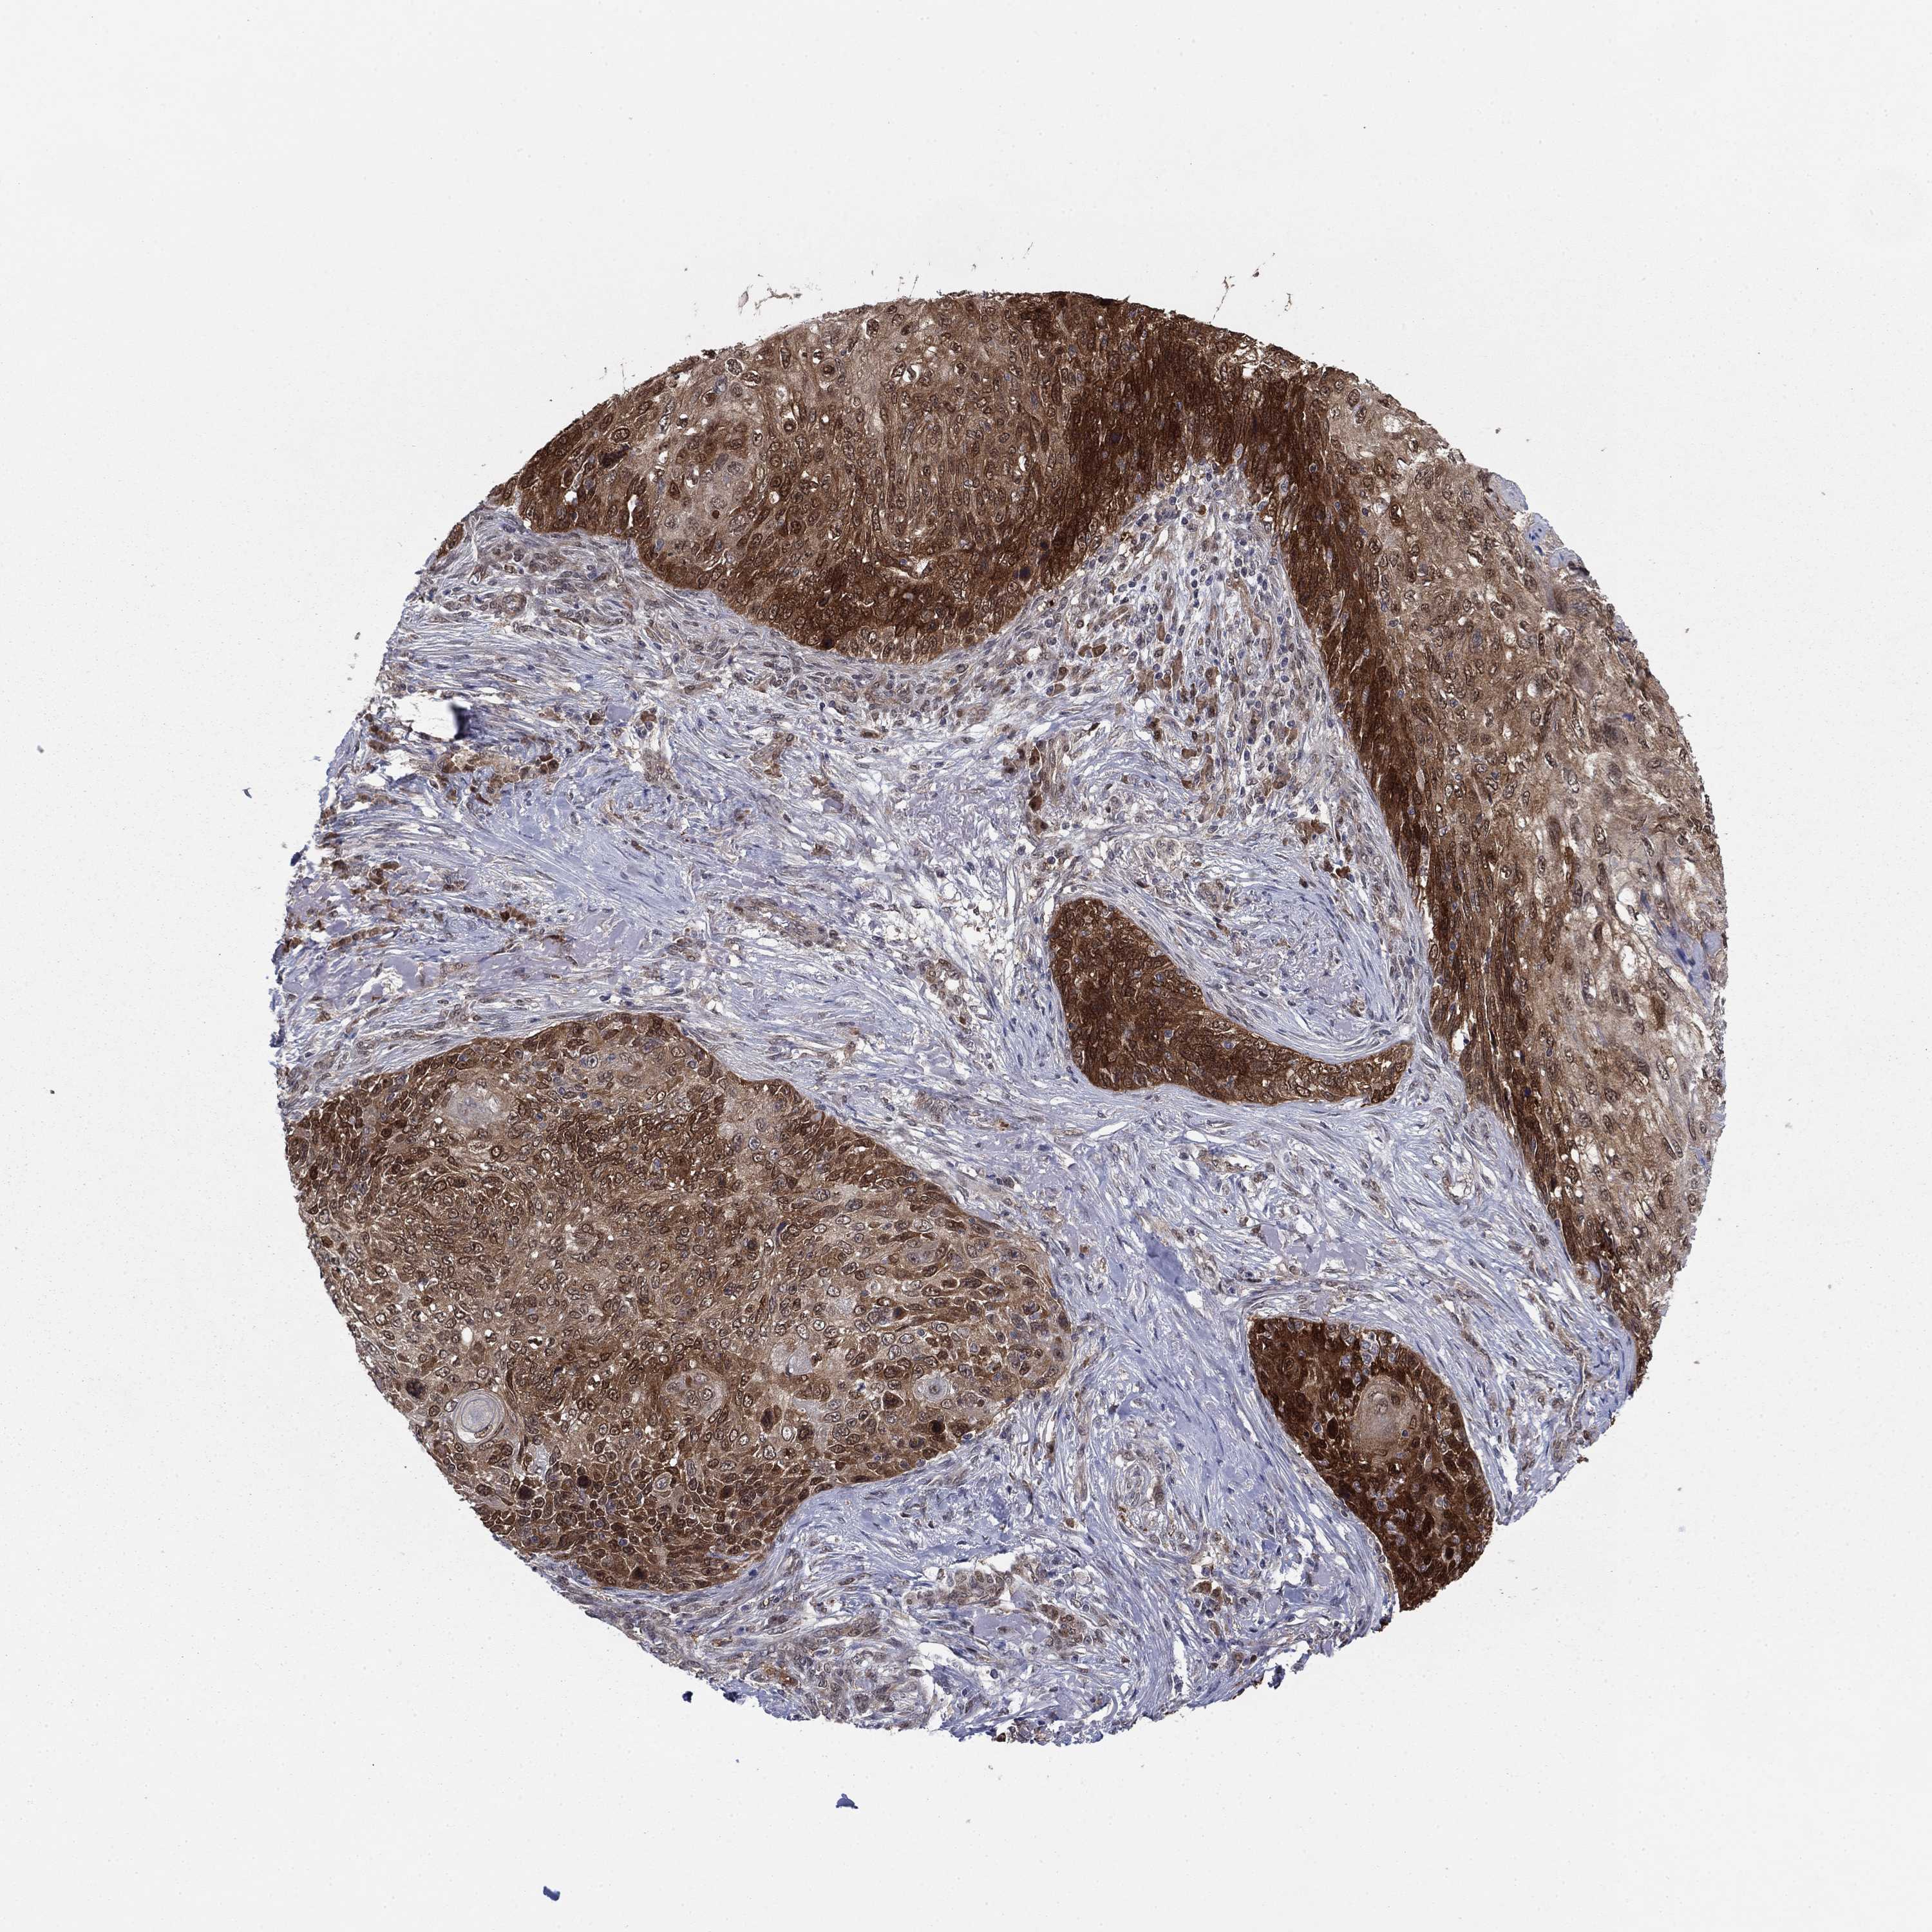

SKIN CANCER - Protein expressioni

A mouse-over function shows sample information and annotation data. Click on an image to view it in a full screen mode. Samples can be filtered based on level of antibody staining by selecting one or several of the following categories: high, medium, low and not detected. The assay and annotation is described here.

Each image is clickable and will lead to virtual microscopy that enables deeper exploration of all samples and also displays staining intensity scores, fraction scores and subcellular localization as well as patient and tissue information for each sample.

Antibody HPA006148

Antibody CAB017441

Staining

High

Strong

>75%

Location

Nuclear

Cytoplasmic/membranous

Cytoplasmic/membranous,nuclear

Squamous cell carcinoma, NOS